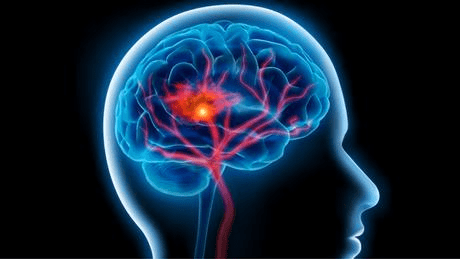

السكتة الدماغية :

السكتة أو الجلطة الدماغية هي ثاني مسبب للوفاة في العالم، ويلقي أكثر من 6 ملايين إنسان حتفهم سنويا بسبب أمراض الدماغ. والسكتة الدماغية هي ليست من أكثر الأمراض المسببة للوفاة فحسب، بل من أخطرها. وتحصل السكتة عندما يقل الأوكسجين في الدماغ. ومن أعراضها حالة الدوار وصداع الرأس وفقدان الرؤية والآلام الكبيرة في الرأس